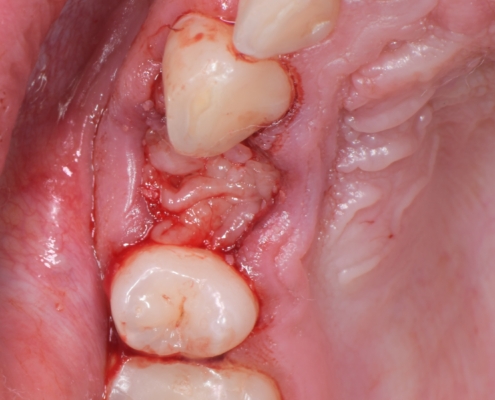

Priprema dentinskog grafta nakon ekstrakcije zuba traje 15–20 minuta., Ekstrakcijska alveola se kohleom očisti od mekih tkiva (Slika 1.). Postupak pripreme dentinskog grafta uključuje temeljito mehaničko čišćenje krune zuba od cakline, ispuna, pigmentacija, karijesa, cementa i protetskih nadomjestaka te korijena zuba od mekih tkiva (Slika 2.). Zub se potom suši pusterom i stavlja u sterilnu jednokratnu komoru uređaja Smart Dentin Grinder (KometaBio inc., Cresskill, NJ, SAD), koji ga usitnjava u čestice veličine između od 300 μm do 1200 μm (Slika 3.) te se potom odvajaju kroz sito uređaja s obzirom na veličinu u za to predviđene pretince (Slika 4.). Usitnjene čestice se zatim kemijski obrađuju otopinom natrijevog hidroksida i alkohola kroz 5 minuta, a nakon toga se dvaput ispiru fiziološkom otopinom puferiranom fosfatima, čime se postiže fiziološki pH od 7,2 (Slika 5.). Preostali vlažni dentinski graft tada je spreman za primjenu u augmentaciji (Slika 6.). Alternativno, usitnjeni dentinski prah može se sterilizirati zagrijavanjem na temperaturu od 140 °C radi potpune eliminacije bakterija, virusa i endotoksina [14]. Usitnjeni veći dijelovi zuba se postavljaju u defekt alveole (Slika 7.), radi bolje regeneracije postavlja se PRGF membrana (Slika 8.) te se završno može postaviti kolagenska spužva za potpunu adaptaciju grafta (Slika 9.). Završno slijedi postava šavova i standardna postoperativna njega.